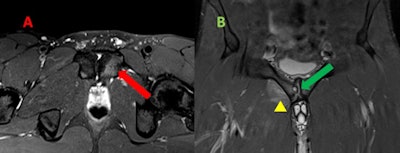

Mild osteitis pubis in a man. A: Transversal T2-weighted fat-suppressed MR image reveals parasymphyseal hyperintensity extending from the subchondral plate of left pubic body, which reflects edema due to increased stress response and areas of trabecular microtrauma. B: Coronal T2-weighted fat-suppressed MR image shows articular surface irregularity, erosions, osteophytes, and subchondral cyst (green arrow). In addition, there is an edema of myotendinous attachments of adductor seen as a coexistent tendinopathy and grade 1 strain (yellow arrowhead).

Mild osteitis pubis in a man. A: Transversal T2-weighted fat-suppressed MR image reveals parasymphyseal hyperintensity extending from the subchondral plate of left pubic body, which reflects edema due to increased stress response and areas of trabecular microtrauma. B: Coronal T2-weighted fat-suppressed MR image shows articular surface irregularity, erosions, osteophytes, and subchondral cyst (green arrow). In addition, there is an edema of myotendinous attachments of adductor seen as a coexistent tendinopathy and grade 1 strain (yellow arrowhead)."As radiographic technology has improved, osteitis pubis is now recognized as a cluster of different injuries to the muscles, tendons, and osseous structures of the lower abdominal wall and pelvis," the researchers pointed out. "The mechanism of injury in athletic pubalgia combines two physical phenomena: repetitive motion injury and muscle development asymmetry."